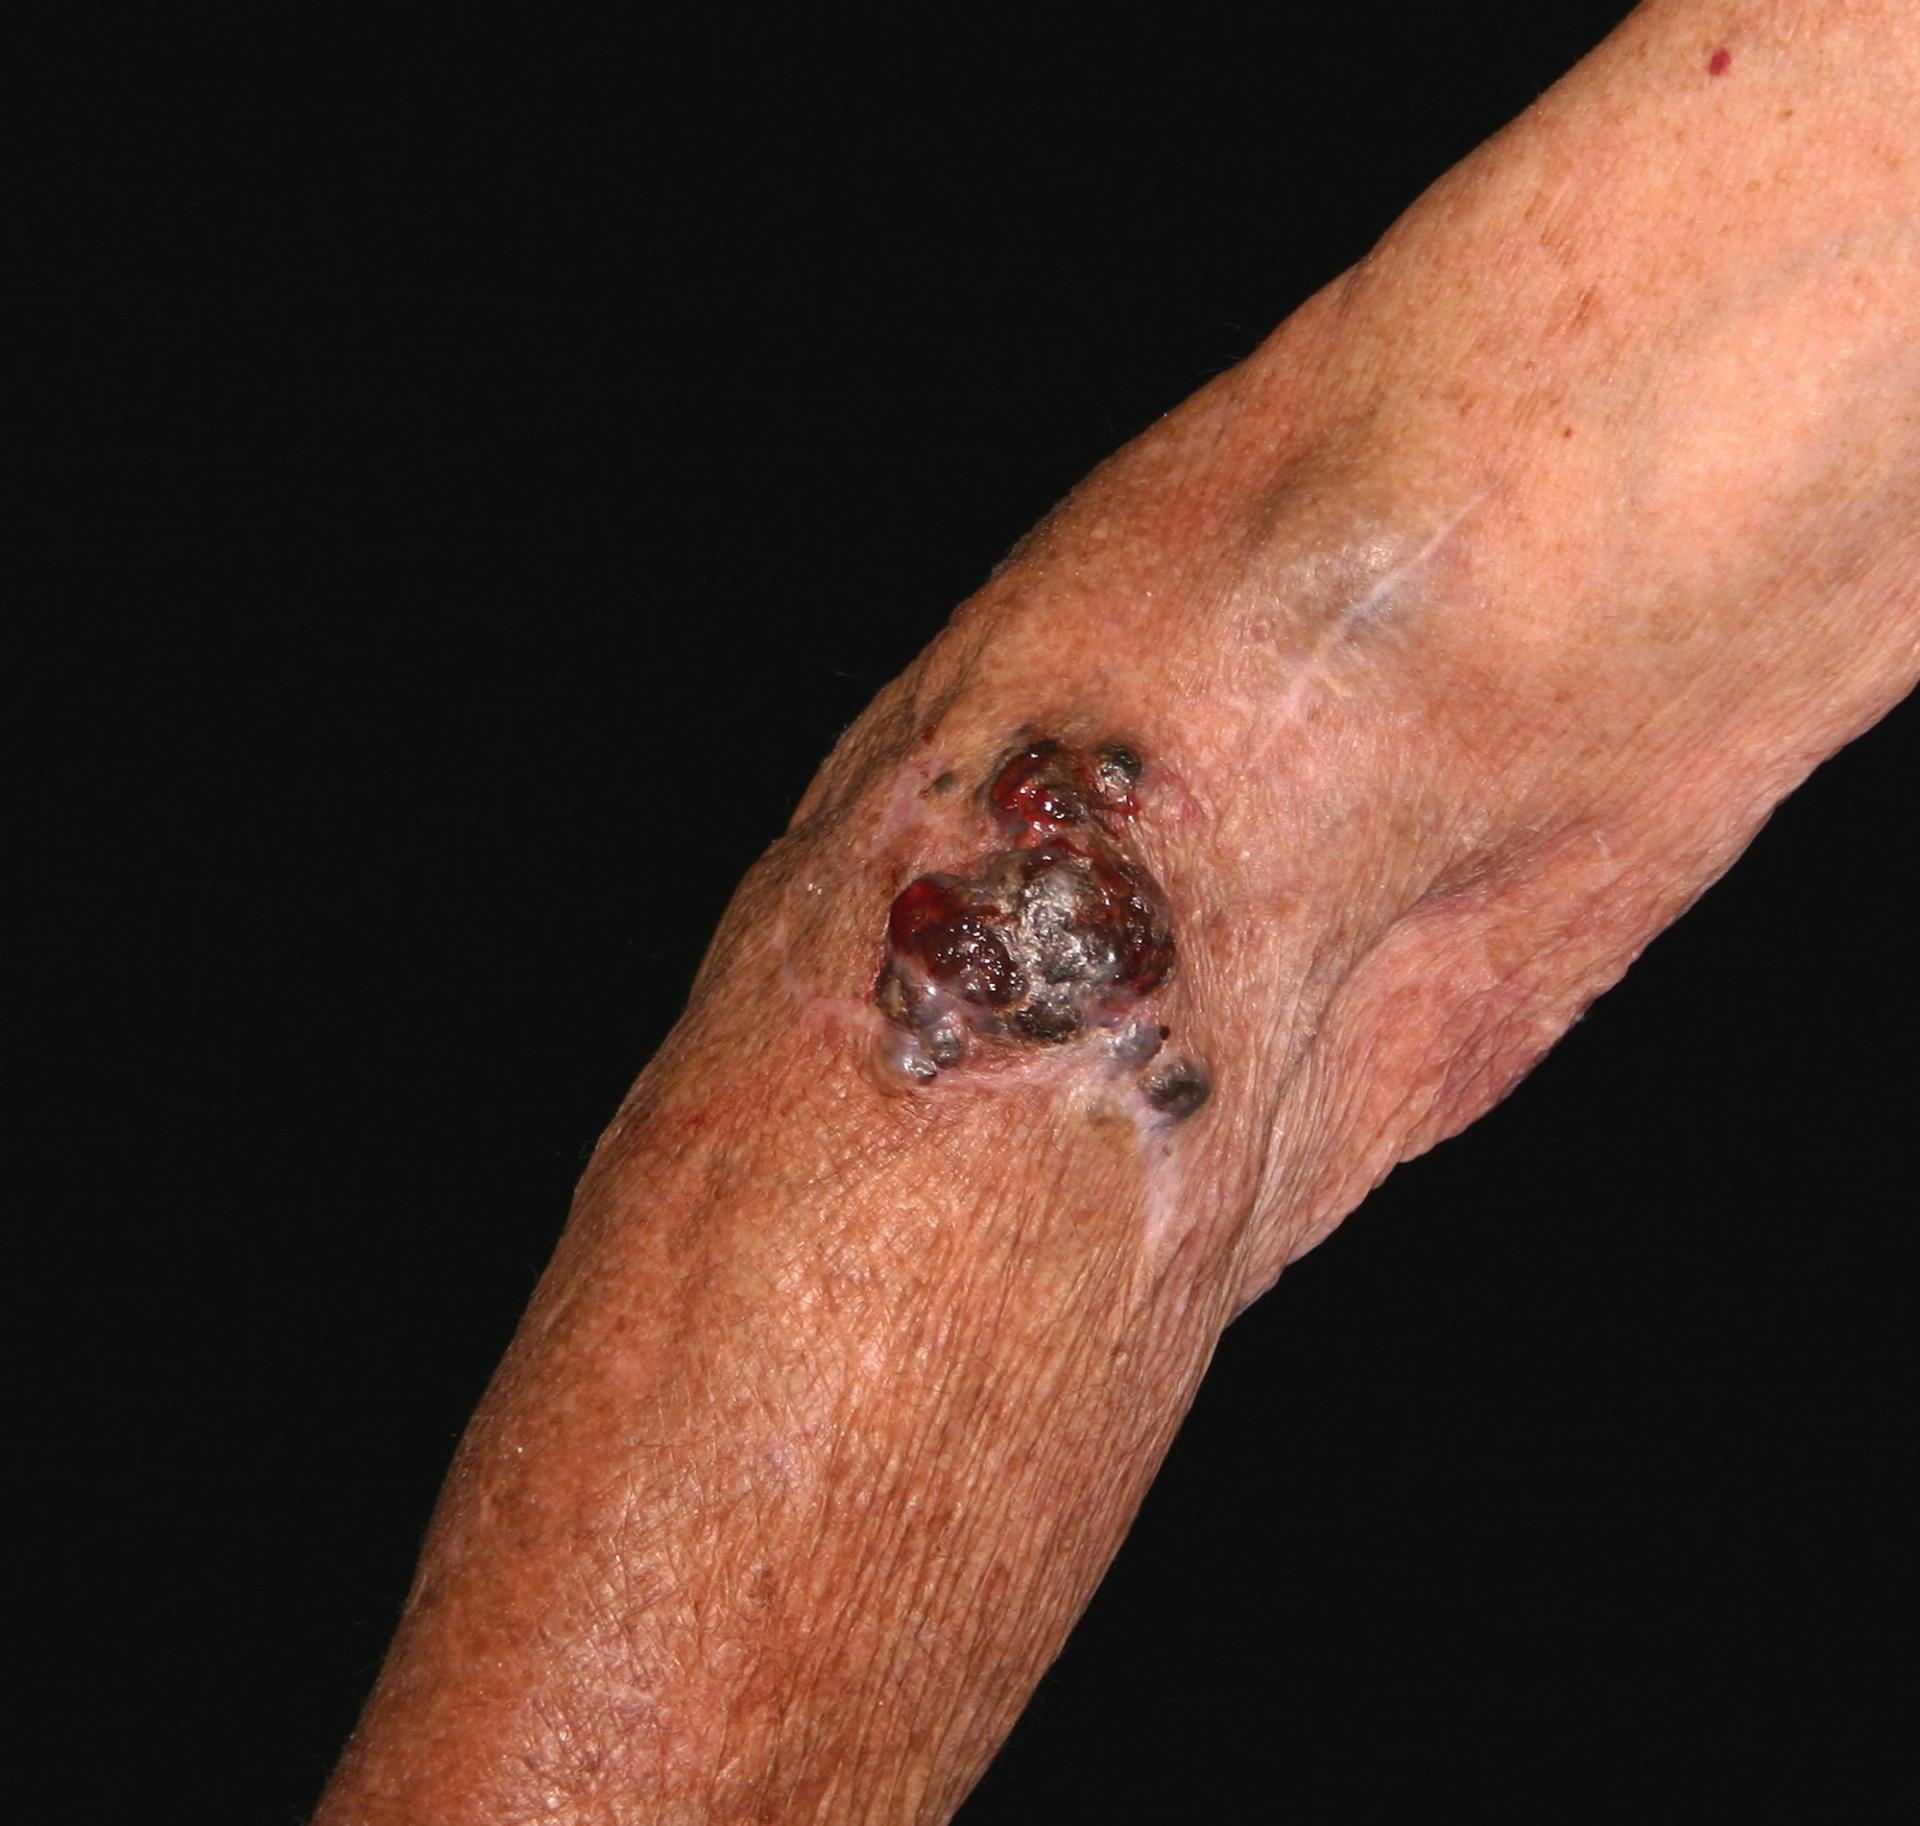

In the case of melanoma, this phase is relatively easy because melanoma has received a lot of attention over the last 40 years, as the increase in foreign package holidays has contributed to an increase in incidence: all types of skin cancer are related to sun exposure, and uniquely, malignant melanoma appears related to episodes of sunburn.4 The process starts when a patient presents to primary care with a mole that they are concerned about.

NICE Clinical Knowledge Summaries (CKS) currently recommend the use of a 7-point checklist (Box 1). A major feature scores 2 points and a minor feature scores 1 point. Anyone with a score of 3 or more should be referred under the ‘Two Week Wait’ protocol, usually to a dermatologist.5 There is a proviso, however, that in situations of high suspicion even one major or minor feature should prompt referral – an obvious example would be when there has been a previous diagnosis of malignant melanoma. The checklist can also be used to reassure patients who probably do not have malignant melanoma.

At the hospital clinic, there will be an examination of your entire patient’s skin, not just the suspicious mole. People with a melanoma are more at risk of having another melanoma, and they may occur on less visible bits of skin, so it makes sense to do a comprehensive inspection. A dermatoscope may be used for this – a piece of equipment that looks like a magnifying glass or camera with a light. The dermatoscope will have a magnifying glass to see the lesion better (typically with a 10X magnification). Also there will be some method of reducing reflection from the skin – older versions used a liquid medium, but newer models overcome this problem by using a polarised light source. A photograph of the mole may be taken.

Next, arrangements will be made for the entire mole to be excised. Together with the mole, a cuff of skin that looks normal will also be removed with at least a 2mm margin, and also some underlying skin fat. This way the thickness of the mole can be determined, which is important for future treatment. The excised tissue is sent to the laboratory to be examined in detail. The wound is sutured.